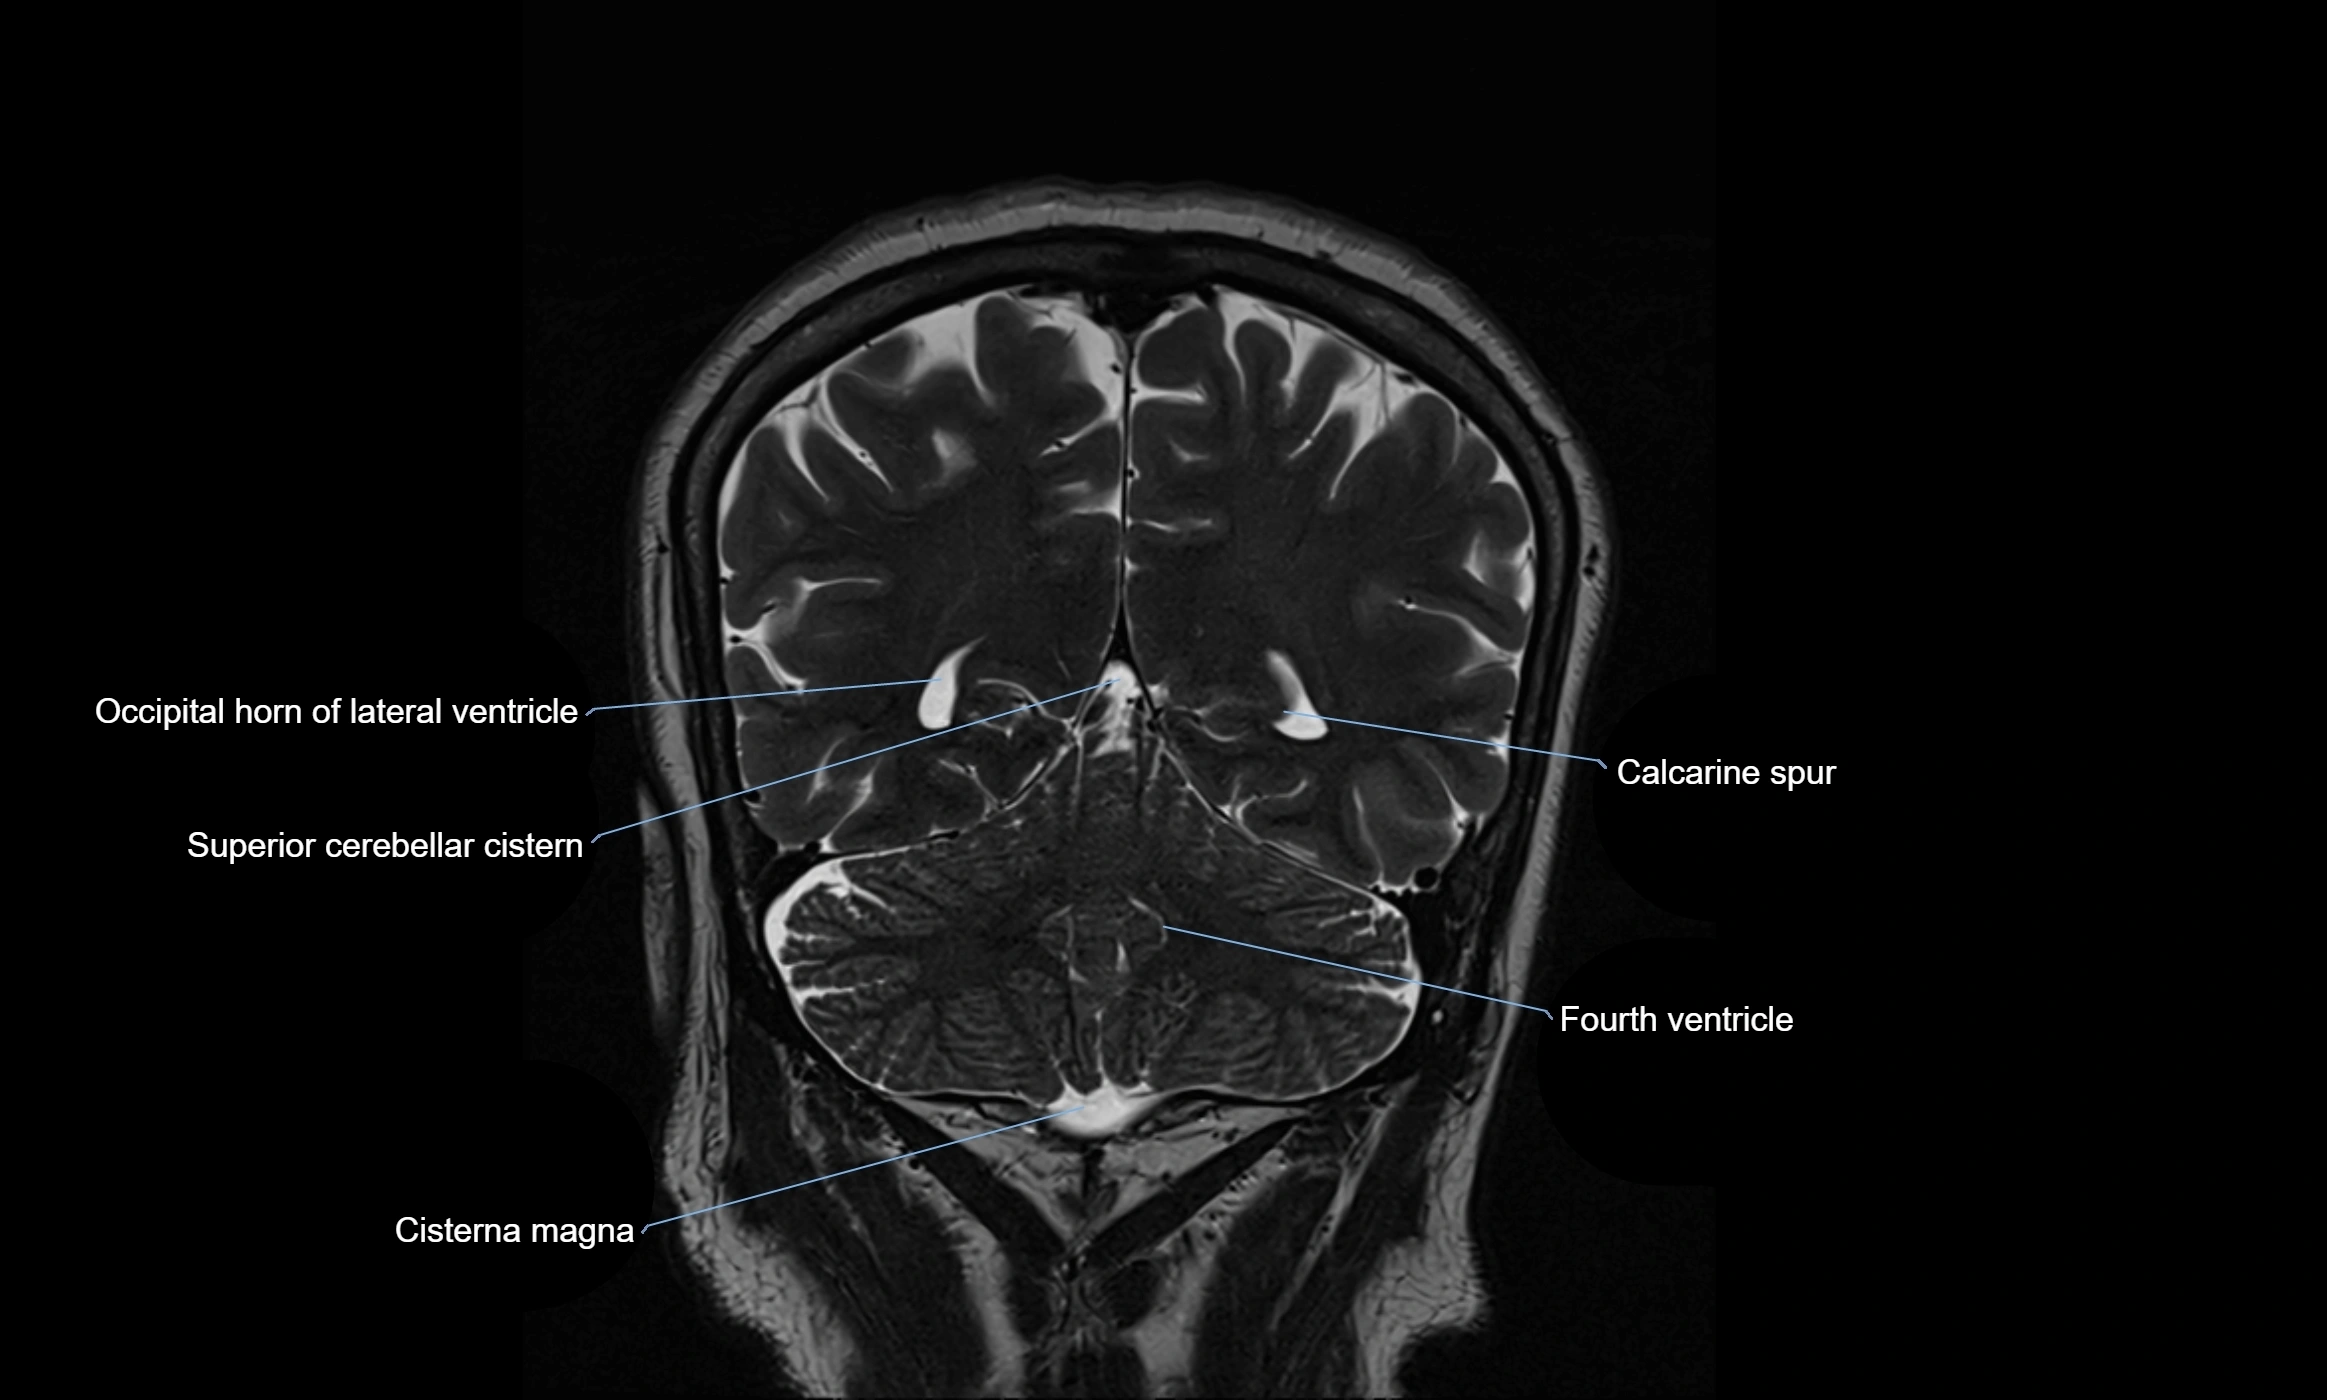

MRI images

image